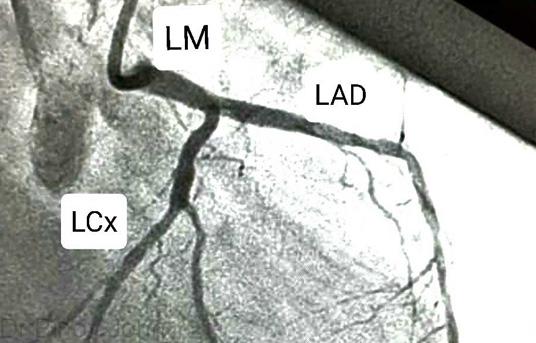

Coronary Angiogram

The heart is a mechanical pump. The function of the heart is to pump blood to the different parts...

View Procedure

What Is Angioplasty?

The function of the heart is to pump blood to different parts of the body. For the heart to...